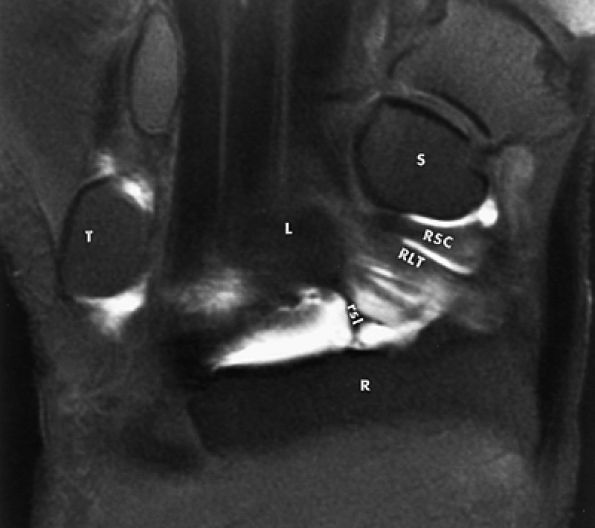

FIGURE 10.62 ● Anatomy of the radioscaphocapitate (RSC), radiolunotriquetral (RLT), and radioscapholunate (rsl) ligaments at the level of the distal volar radius (R). T, triquetrum; S, scaphoid. FS T1-weighted arthrogram after radiocarpal injection.

FIGURE 10.63 ● The long radiolunate or radiolunotriquetral (RLT) ligament. (A) The RLT ligament is divided into a radiolunate ligament and lunotriquetral component. The RLT ligament functions as a volar sling for the lunate. L, lunate; R, radius. Volar FS coronal T1-weighted arthrogram. FS axial T1-weighted arthrograms obtained at the level of the proximal (B) and distal (C) aspects of the radial styloid show the volar course of the RLT ligament (large arrows) from the radial styloid (R) inserting into the lunate (L) and blending with the volar portion of the lunotriquetral interosseus ligament. The lunate attachment of the scapholunate interosseous ligament volar fibers is deep to the lunate attachment of the RLT ligament (B). S, scaphoid; T, triquetrum; SL, scapholunate ligament.